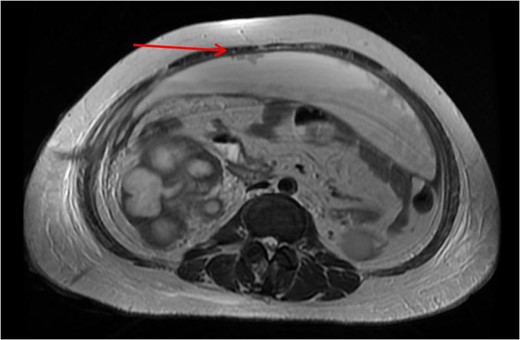

Xanthogranulomatous pyelonephritis (XGPN) is a rare form of chronic pyelonephritis with progressive loss of renal function. Commonly, obstructing urinary calculi are seen. It is difficult to differentiate between XGPN and malignancy in many cases, and the diagnosis is usually only confirmed post-operatively upon histopathological examination of the specimen. Surgical treatment is often the main treatment modality due to suspicion for malignancy. Here, we present a case of XGPN that presented with abdominal distension, which was eventually discovered to be due to a preperitoneal abscess.

She underwent insertion of a right percutaneous nephrostomy drain, percutaneous drainage of the anterior abdominal collection, as well as a percutaneous biopsy of the right renal soft tissue lesion. Urine cultures from the percutaneous nephrostomy grew Proteus mirabilis. Fluid cytology from the abdominal collection showed acute inflammatory cells. Biopsy of the renal lesion showed xanthogranulomatous inflammation.

Our patient had an atypical presentation with abdominal distension and presumed ascites, which was eventually revealed to be an anterior preperitoneal collection secondary to infection. Although the initial suspicion was that of a malignant process complicated by ascites, subsequent cytology and histopathological results showed that it was likely benign. In view of the non-functioning renal unit and significant abdominal collection, she underwent definitive surgery.

The most common urinary pathogen identified was Escherichiacoli [3], and common areas of involvement were the retroperitoneum and psoas muscle. In our patient, the retroperitoneal space was surprisingly not greatly involved, but rather it was the anterior preperitoneal space that had significant adhesions and inflammation. The pathogen identified from both nephrostomy and preperitoneal collection was P. mirabilis, showing that both pathologies were linked.